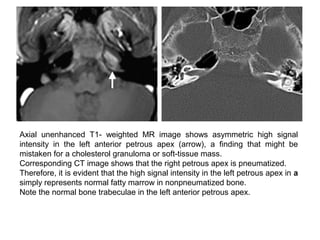

Axial unenhanced T1- weighted MR image shows asymmetric high signal

intensity in the left anterior petrous apex (arrow), a finding that might be

mistaken for a cholesterol granuloma or soft-tissue mass.

Corresponding CT image shows that the right petrous apex is pneumatized.

Therefore, it is evident that the high signal intensity in the left petrous apex in a

simply represents normal fatty marrow in nonpneumatized bone.

Note the normal bone trabeculae in the left anterior petrous apex.